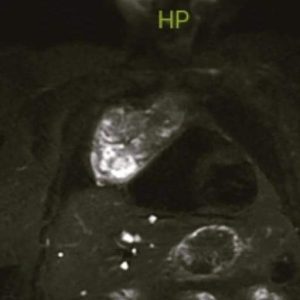

Kalp komşuluğunda Göğüs boşluğu yerleşik kitle tespit edilen hasta, Ordu Üniversitesi Eğitim ve Araştırma Hastanesi başarılı bir ameliyatla sağlığına kavuştu.

Ordu Üniversitesi Eğitim ve Araştırma Hastanesi Göğüs Cerrahisi Kliniği Doktoru Doç. Dr. Barış Hekimoğlu tarafından, sırt ağrısı ve aritmi (ritim bozukluğu) şikayeti ile gelen hastada kalp komşuluğunda mediastene (Göğüs boşluğu) yerleşik kitle tespit edildi ve hasta başarılı bir ameliyatla sağlığına kavuştu.